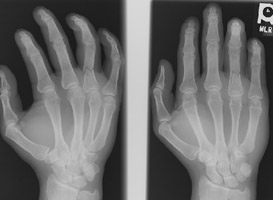

- Click on the image for a larger versionALateral radiograph of the hand. This demonstrates an angulated fracture of the fourth proximal phalanx.

- Click on the image for a larger versionBPA and oblique radiographs of the hand. The also show the fracture of the fourth proximal phalanx.